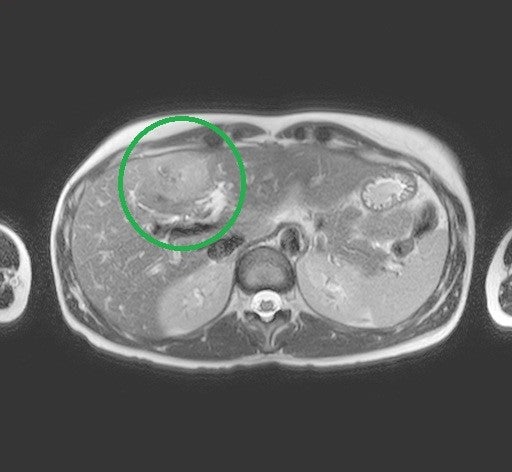

1/2025 MRCP s nejasným ložiskem SIVb jater velikosti 55x42x47 mm

Obr. 1: MRCP s nejasným ložiskem SIVb jater velikosti 55x42x47 mm